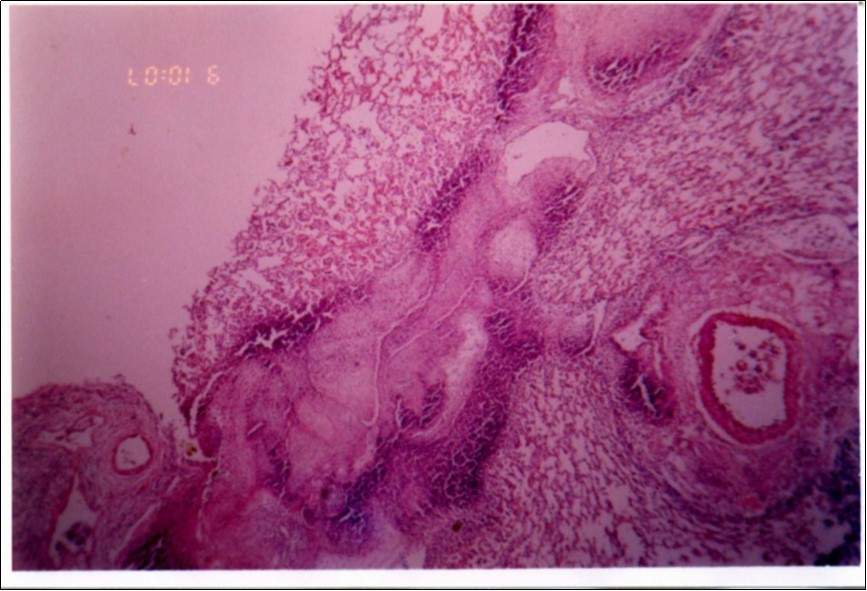

Figure 3, Figure 4 and Figure 5 show different histopathological pictures of hepatized lung tissue samples from which Mmm isolates were recovered. In Figure 3, widened interlobular septa, due to presence of fibrinous necrosis and cellular infiltration were observed. Figure 4 shows extensive loss of airspace due to necrosis and infiltration of neutrophils. Figure 5 shows hyperemia of alveolar wall capillaries and infiltration of few fibrin and neutrophils.

Figure 3.Widened interlobular septa in pneumonic lung tissue (H&E ×200).

Although no advanced techniques like PCR were used to identify the isolates, procedures used in this study were quite enough to confirm the incidence. Affected animals with CBPP were diagnosed based on the clinical signs, the PM findings, the typical histopathological picture in addition to the isolation of the causative agent and its subsequent identification using cultural and biochemical procedures. Identification of the isolates was confirmed by the growth inhibition test as recommended in OIE manual 10. The histopathological sections of diseased lungs, from which Mmm (SC) was isolated, showed typical histopathological picture of CBPP. The CBPP lesion comprises abronchiolar necrosis and oedema which progress rapidly to an exudative serofibrinous bronchiolitis with extension to the alveoli and uptake of alveolar fluid into tissue spaces 17, lymphatic vessels and ultimately septal lymphatics 18. With stasis, lymphatic vessels become thrombosed and ultimately fibrosed 19. The histological section of the lung in acute stage of the disease showed odema in the lymphatics of the interlobular septa and interstitial tissue and massive infiltration of fibrin, macrophage and neutrophils into the alveolar lumen 20. Also there was presence of lymphocytes and alveolar macrophages around the lymphatic vessels and septa margin 21. These findings supported the isolation results and gave additional evidence for the diagnosis of the disease.